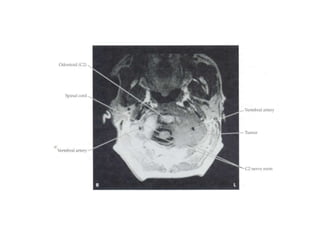

RAIZES NERVOSAS XVERTÉBRAS, DISCOS E LIGAMENTOS